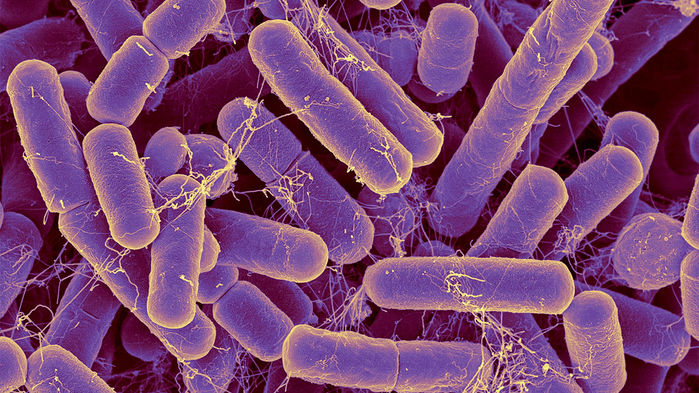

Bacteroides are the most common bacteria species found in the human intestinal tract. Dennis Kunkel Microscopy/Science Source

The idea that you can predict someone’s age based on their gut microbiome is “very plausible” and of “tremendous interest” to scientists.

Dr. Zhavoronkov, longevity researcher at InSilico Medicine, Maryland and computer scientist and microbiome researcher, Robin Knight, director of the Center for Microbiome Innovation at the University of California, San Diego, and colleagues found out how the microbiome changes over time by examining more than 13,000 samples of gut bacteria from healthy individuals living across the globe.

The human gut microbiome is a complex ecosystem that both affects and is affected by its host status. Zhavoronkov says this “microbiome aging clock” could be used as a baseline to test how fast or slow a person’s gut is aging

Previous analyses of gut microflora revealed associations between specific microbes and host health and disease status, genotype and diet.

Here, we developed a method of predicting biological age of the host based on the microbiological profiles of gut microbiota using a curated dataset of 1,165 healthy individuals (3,663 microbiome samples).